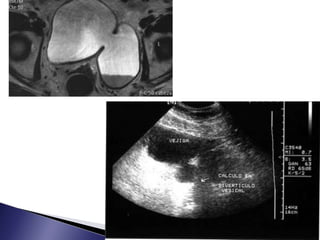

 Ecografía

 Descarta malformaciones

congénitas renales

 Evalúa tamaño renal y

morfología

 58% identifica litiasis

 Valora ecogenicidad el

parénquima y si existe o no

edema

 Distingue presencia minima de

liquido perirrenal subcapsular

por las disrrupciones del

fórnix

 Alternativa aUIV en pacientes con IRC  Se visualiza el trayecto afectado dilatado que maneja 10UH y hasta 30UH en pionefrosis  Visualiza litiasis y el tejido periureteral  Discrimina si la obstrucción es intrínseca o extrínseca

 Ecografía  Descartamalformaciones congénitas renales  Evalúa tamaño renal y morfología  58% identifica litiasis  Valora ecogenicidad el parénquima y si existe o no edema  Distingue presencia minima de liquido perirrenal subcapsular por las disrrupciones del fórnix